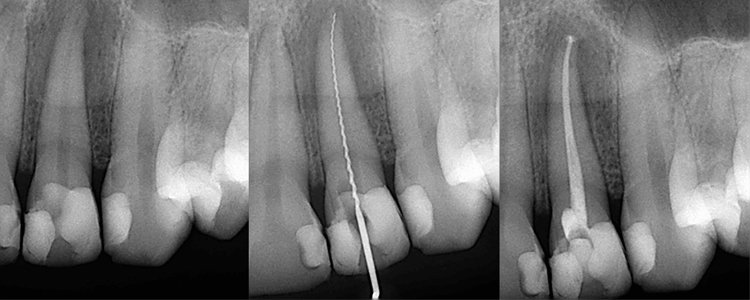

L’endodontie traite les infections de la pulpe dentaire afin de sauver la dent naturelle. Lorsque la carie atteint le nerf, un traitement canalaire est nécessaire pour éliminer l’infection et préserver la structure dentaire.

Un retraitement peut être indiqué en cas d’échec d’un ancien traitement. Les urgences pulpaire et péri-apicales sont prises en charge rapidement pour soulager la douleur.

Sauver la dent est toujours préférable à son extraction.